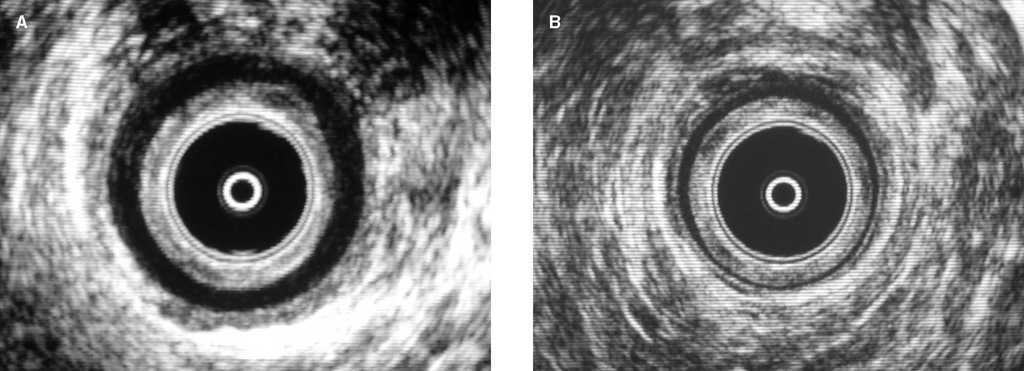

La ecografía endoanal mostró que el grosor del EAI estaba aumentado en 58 (92%) pacientes (fig. 1) y observamos que había una correlación positiva con la edad (r = 0,4; p < 0,001). El grosor medio del EAI fue de 3,7 ± 0,7 mm. No encontramos diferencias significativas entre varones y mujeres (3,5 ± 0,7 frente a 3,8 ± 0,7 mm; p = 0,06). No observamos defectos en el EAI ni en el EAE en ninguno de los pacientes de este estudio.

Fig. 1. Ecografía endoanal que muestra un esfínter anal interno (EAI) hipertrófico, con un grosor de 4,2 mm determinado en el canal anal medio (A) comparado con un EAI normal de 2,1 mm de grosor máximo (B).